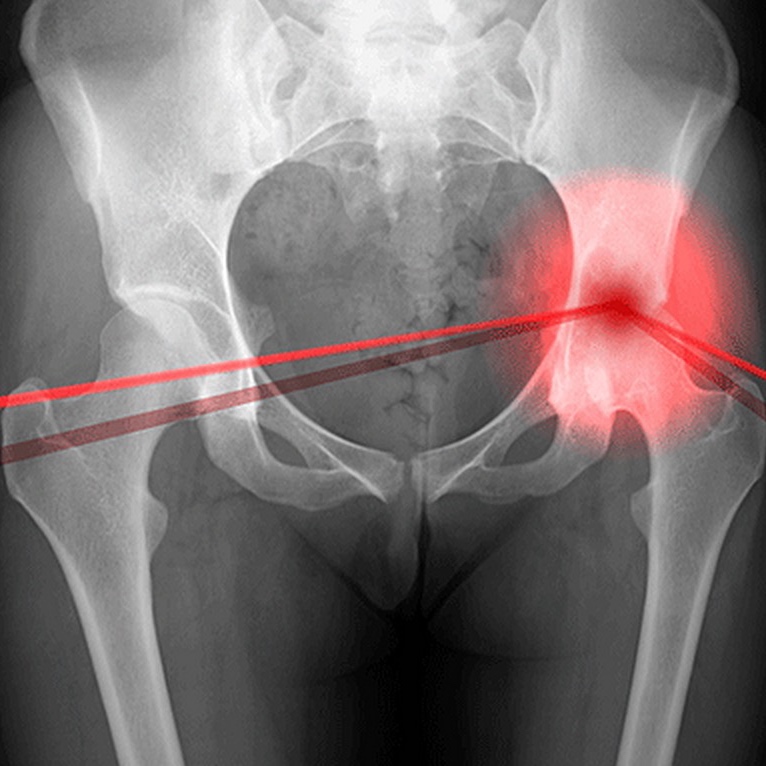

Рентгеновские снимки: Синовит тазобедренного сустава